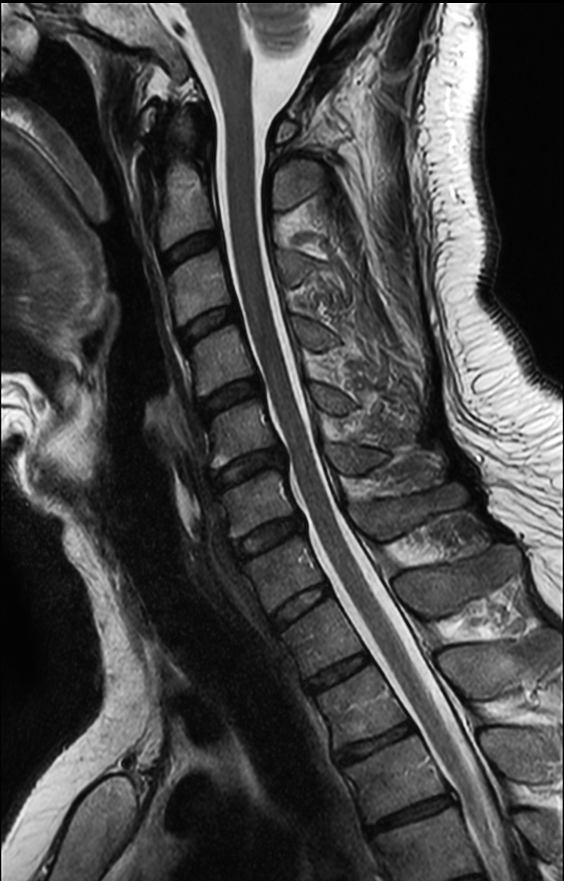

Comprehensive Cervical Spine imaging at 3.0T